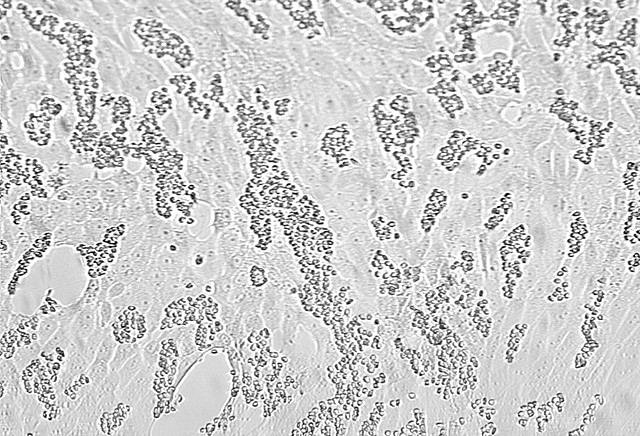

• CDC successfully grows Sars-Cov-2 virus in cell culture

CDC successfully grows Sars-Cov-2 virus in cell culture

By successfully growing the SARS-CoV-2 virus in cell culture, this opens up the door for many further research studies on the virus, like antiviral treatments and vaccine development. The CDC has also sent samples of the virus to the Biodefense and Emerging Infections Research Resources Repositry, such that researchers and establishments can request and receive samples for free. Image shows a cell culture infected with influenza virus.